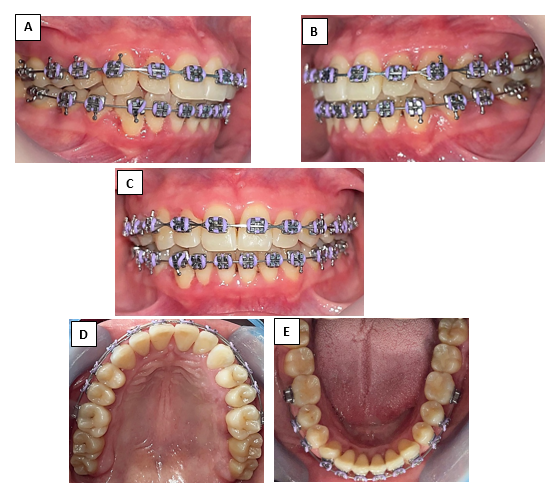

Figura  7  A) Right lateral view, B) Left lateral view, C) Frontal view, D) Upper occlusal view, E) Lower occlusal view.